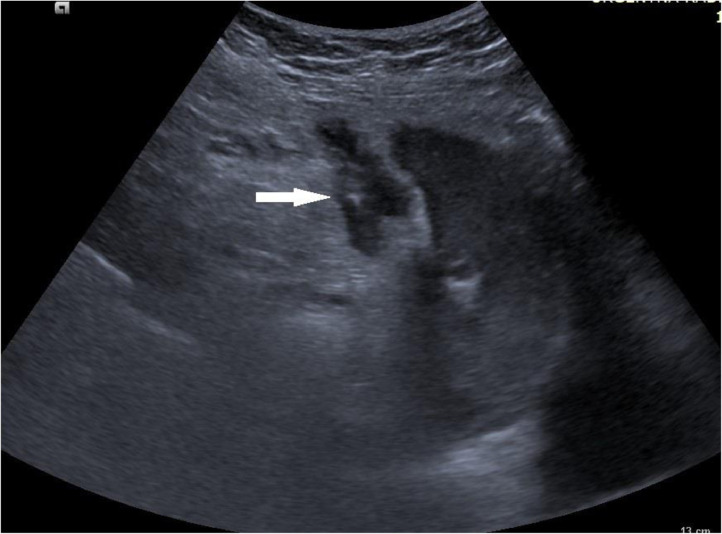

Fig. 2.

Abdominal ultrasound: transverse scan in epigastrium showed abscess in falciform ligament (arrow).